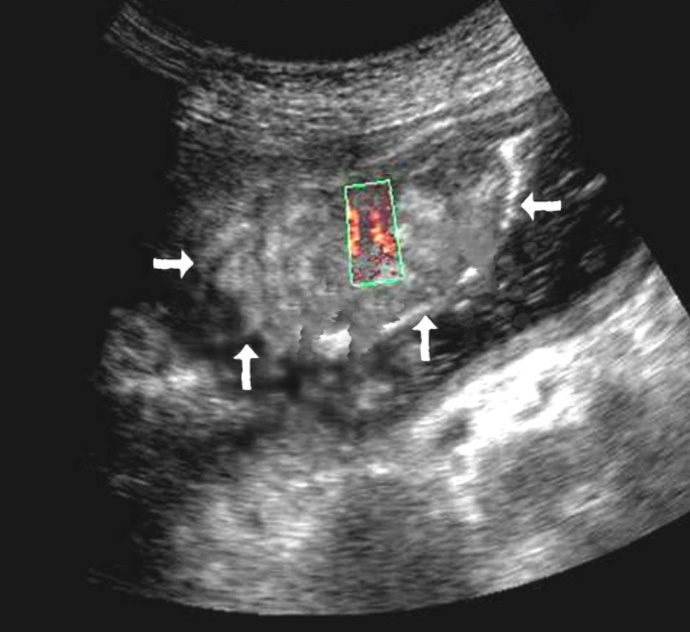

Among the 61 patients, pathological vascularization was detected in 42 (68.8%) cases. Of these, all 4 (6.5%) patients with gastric cancer were stage T4 and 38 (62.3%) were stage T3. In 13 cases, vascularization was weak, in 24 cases - moderate, and in 5 cases - enhanced.

Weak vascularization was manifested in the form of a single point color vascular signals, the moderate vascularization - in the form of linear color vascular signals and the enhanced vascularization - in the form of wide color areas inside the tumor (Figure 16, Figure 17).

Figure 16.Distal gastric carcinomas of diffuse infiltrative form of T4 stage. Despite the large size of the tumor the vascularization is manifested in the form of single point color vascular signals.

Figure 17.Gastric carcinomas of infiltrative ulcerative form of Ts stage. Despite the small size of the tumor the vascularization is manifested in the form of wide color areas inside the tumor.